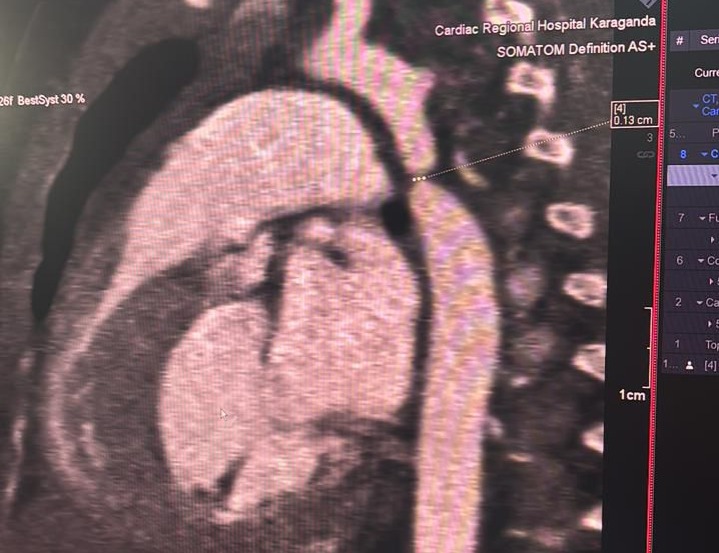

Маленькое сердце – большая победа: в Караганде впервые провели сложную операцию трехмесячной девочке

Фото: ФСМС Караганды 2 марта этого года стало важной датой для карагандинской медицины. В Многопрофильной больнице № 2 впервые успешно провели сложную операцию на сердце трехмесячной девочке. Жизнь ребенка спасала команда врачей из Караганды и Астаны, передает корреспондент ekaraganda.kz со ссылкой на Фонд социального медицинского страхования Караганды.

История началась с госпитализации малышки с пневмонией в городскую многопрофильную больницу № 1. Однако во время обследования медики обнаружили куда более серьезную проблему – критическую коарктацию аорты. Это опасный врожденный порок, при котором происходит резкое сужение главного сосуда организма, что без своевременного вмешательства может привести к тяжелым последствиям.

О диагнозе сразу сообщили родителям, после чего ребенка экстренно перевели в кардиоцентр. Там провели консилиум и приняли решение оперировать девочку в рамках мастер-класса с участием ведущих кардиохирургов страны. Для этого из UMC (University Medical Center) были приглашены кардиохирург Галымжан Утегенов и анестезиолог Хафиз Ахмеров.

Операция длилась около пяти часов и требовала высокой точности. Хирурги выполнили резекцию коарктации аорты с наложением анастомоза «конец в конец», тем самым восстановив нормальный кровоток. Во время вмешательства врачи также обнаружили открытый артериальный проток: его удалось успешно легировать.

Кардиохирург Галымжан Маликович отметил:

«Критическая коарктация аорты у детей первых месяцев жизни – это состояние, требующее срочного хирургического вмешательства. Операция была непростой, но прошла в плановом режиме. Нам удалось полностью устранить сужение и сопутствующую патологию. Сейчас все зависит от послеоперационного восстановления, состояние ребенка стабильное и внушает оптимизм».

Для региона это событие стало по-настоящему историческим. Заведующий отделением детской кардиохирургии МБ № 2 Ганибек Акжанов подчеркнул значимость события для Караганды.

«Это первая подобная операция, проведенная в стенах нашей больницы. Раньше таких пациентов направляли в республиканские центры. Благодаря сотрудничеству с коллегами из столицы мы смогли оказать высокотехнологичную помощь на месте. Это серьезный шаг вперед для развития детской кардиохирургии в Караганде», – подытожил Акжанов.

Ранее маленьких пациентов с подобными диагнозами действительно приходилось отправлять в крупные республиканские клиники. Теперь высокотехнологичную помощь можно получить и в Караганде.

После операции девочка находится в реанимации под постоянным контролем специалистов. Врачи отмечают положительную динамику и осторожно говорят о хорошем прогнозе. Родители ребенка искренне поблагодарили спасителей.

«Мы даже не знали, что у нашей девочки есть порок сердца. Это стало для нас шоком. Но врачи сработали очень быстро. Операция длилась почти пять часов, и все это время мы молились. Самое главное, что все прошло успешно. Мы ничего не платили, все было бесплатно в рамках медицинского страхования. Огромная благодарность всем врачам за спасенную жизнь нашей дочери», – не скрывая эмоций, поделился отец девочки.

Этот случай стал не только спасением одной маленькой жизни, но и важным этапом в развитии детской кардиохирургии региона. Для карагандинских врачей – это новый уровень возможностей. Для родителей – второй день рождения их дочери.